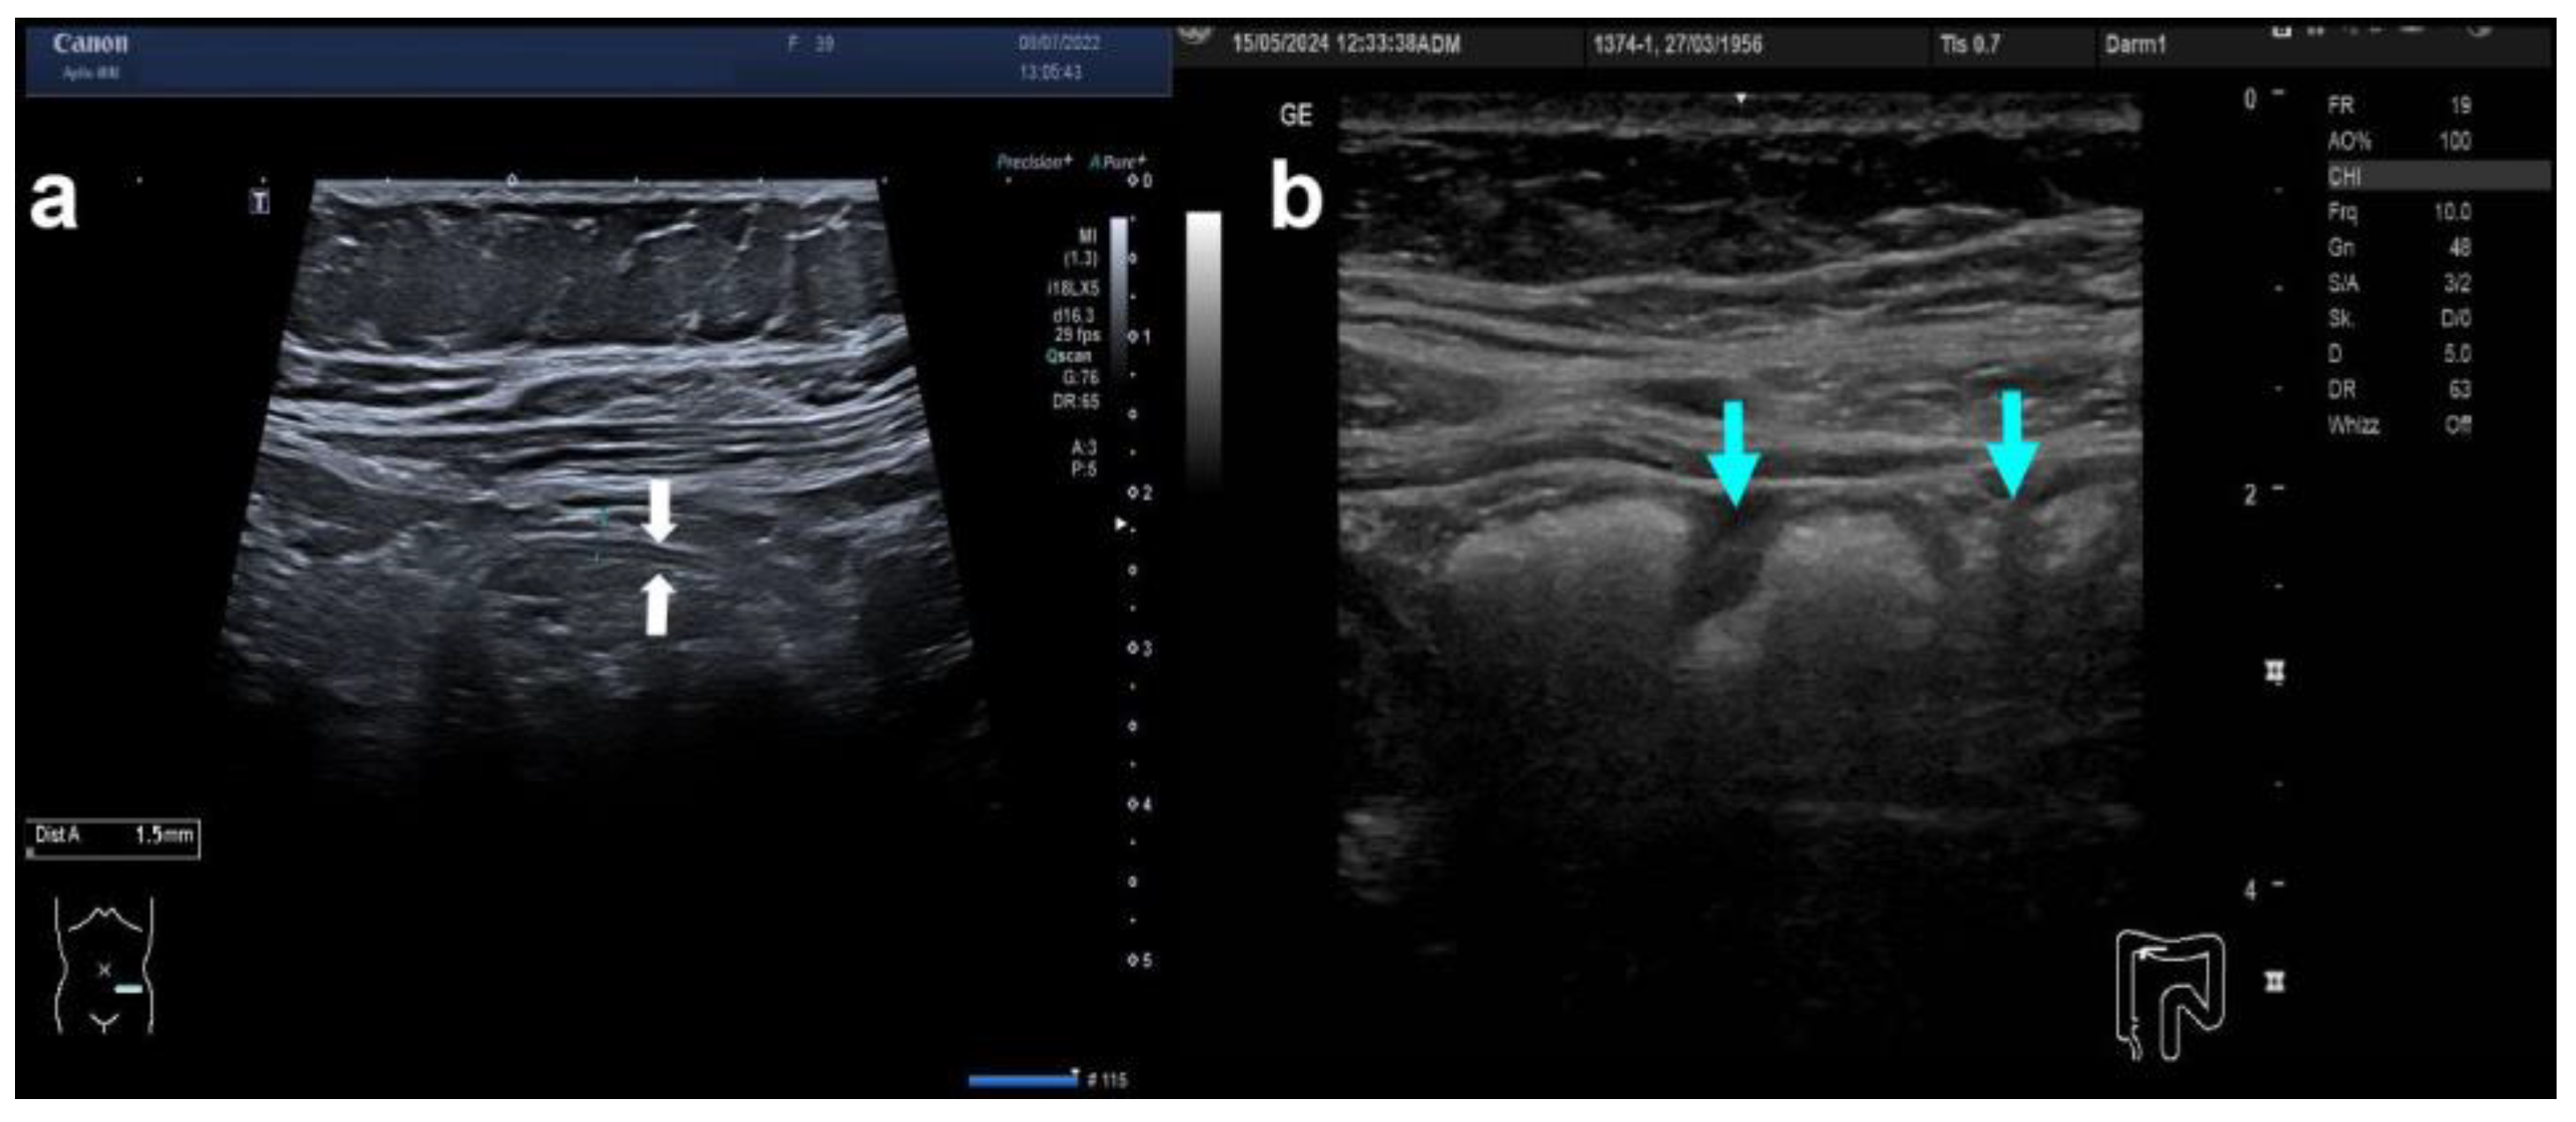

| Bowel wall | Bowel wall thickness (BWT) | [in mm (>3 mm without increased vascularity: Limberg 1)] | |

| Bowel wall stratification (BWS) | [preserved stratification; blurred stratification; localised loss of stratification; generalised loss of stratification] | ||